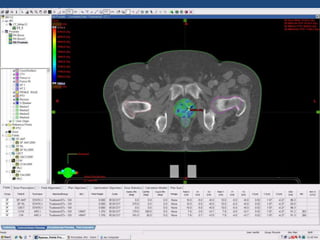

Prostate cancer is the second most common cancer globally, with varying incidence rates influenced by geography and lifestyle changes. In India, prostate cancer cases are rising due to urban migration and increased medical awareness, with current rates approaching those in Western countries. Treatment options vary by stage, including watchful waiting, surgery, radiation therapy, and hormonal treatment, each tailored to patient-specific factors.